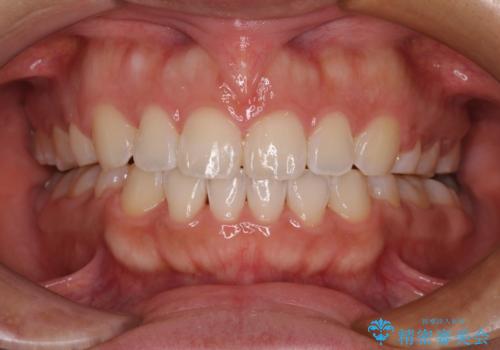

上顎歯列を遠心移動させたことで、前歯の叢生が解消されても前歯が前突することなく、左右ともに理想的な咬み合わせを達成することができました。